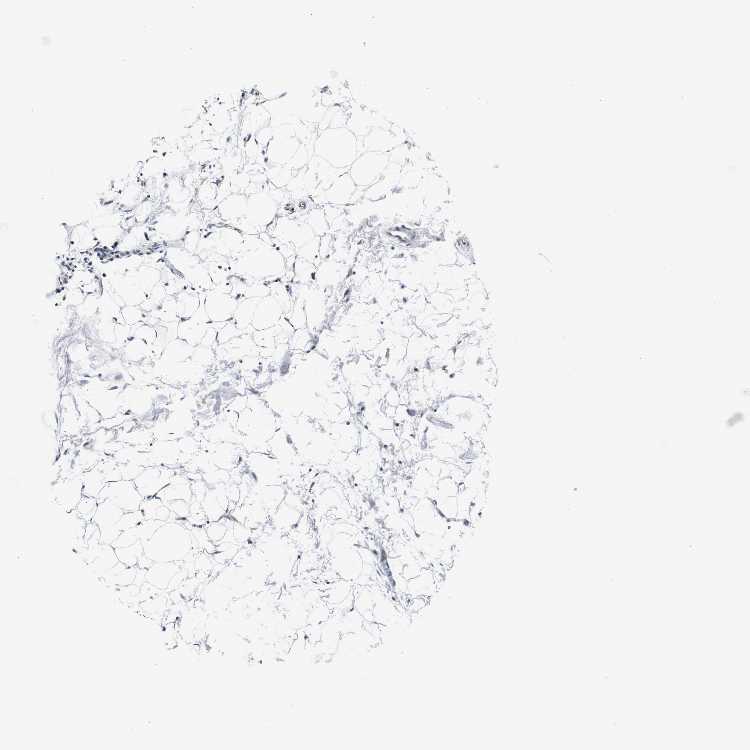

SOFT TISSUE 2 - Antibody stainingi

Antibody staining in the annotated cell types in the current human tissue is reported as not detected, low, medium, or high, based on conventional immunohistochemistry profiling in selected tissues. This score is based on the combination of the staining intensity and fraction of stained cells.

Each image is clickable and will lead to virtual microscopy that enables deeper exploration of all samples and also displays staining intensity scores, fraction scores and subcellular localization as well as patient and tissue information for each sample.

Antibody HPA013316Antibody CAB002496

Fibroblasts Not detectedNot detected

Peripheral nerve Medium-